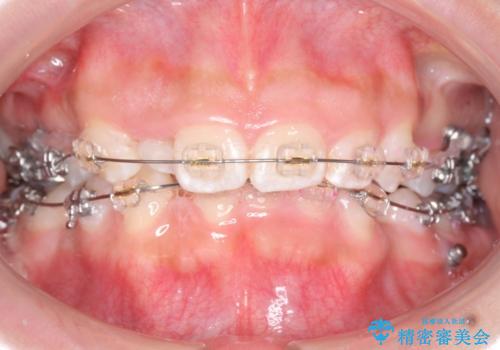

- 矯正装置

- プラスチックブラケット

奥歯のかみ合わせもずれていたため、上の奥歯を後ろに下げる処置をミニスクリューを用いて行いました。